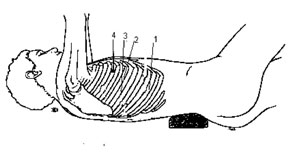

O procedimento cirúrgico foi realizado

exclusivamente por videotoracoscopia, com o paciente em decúbito lateral esquerdo.

Utilizamos quatro acessos no hemitórax direito: punções

de 10mm nos 70 e 110 espaços intercostais,

linha axilar média, de 5 mm no

80 espaço intercostal na linha hemiclavicular e outro de 5 mm no

100 espaço intercostal na linha axilar posterior.

|

|

| Figura 2 - Posição das punções |